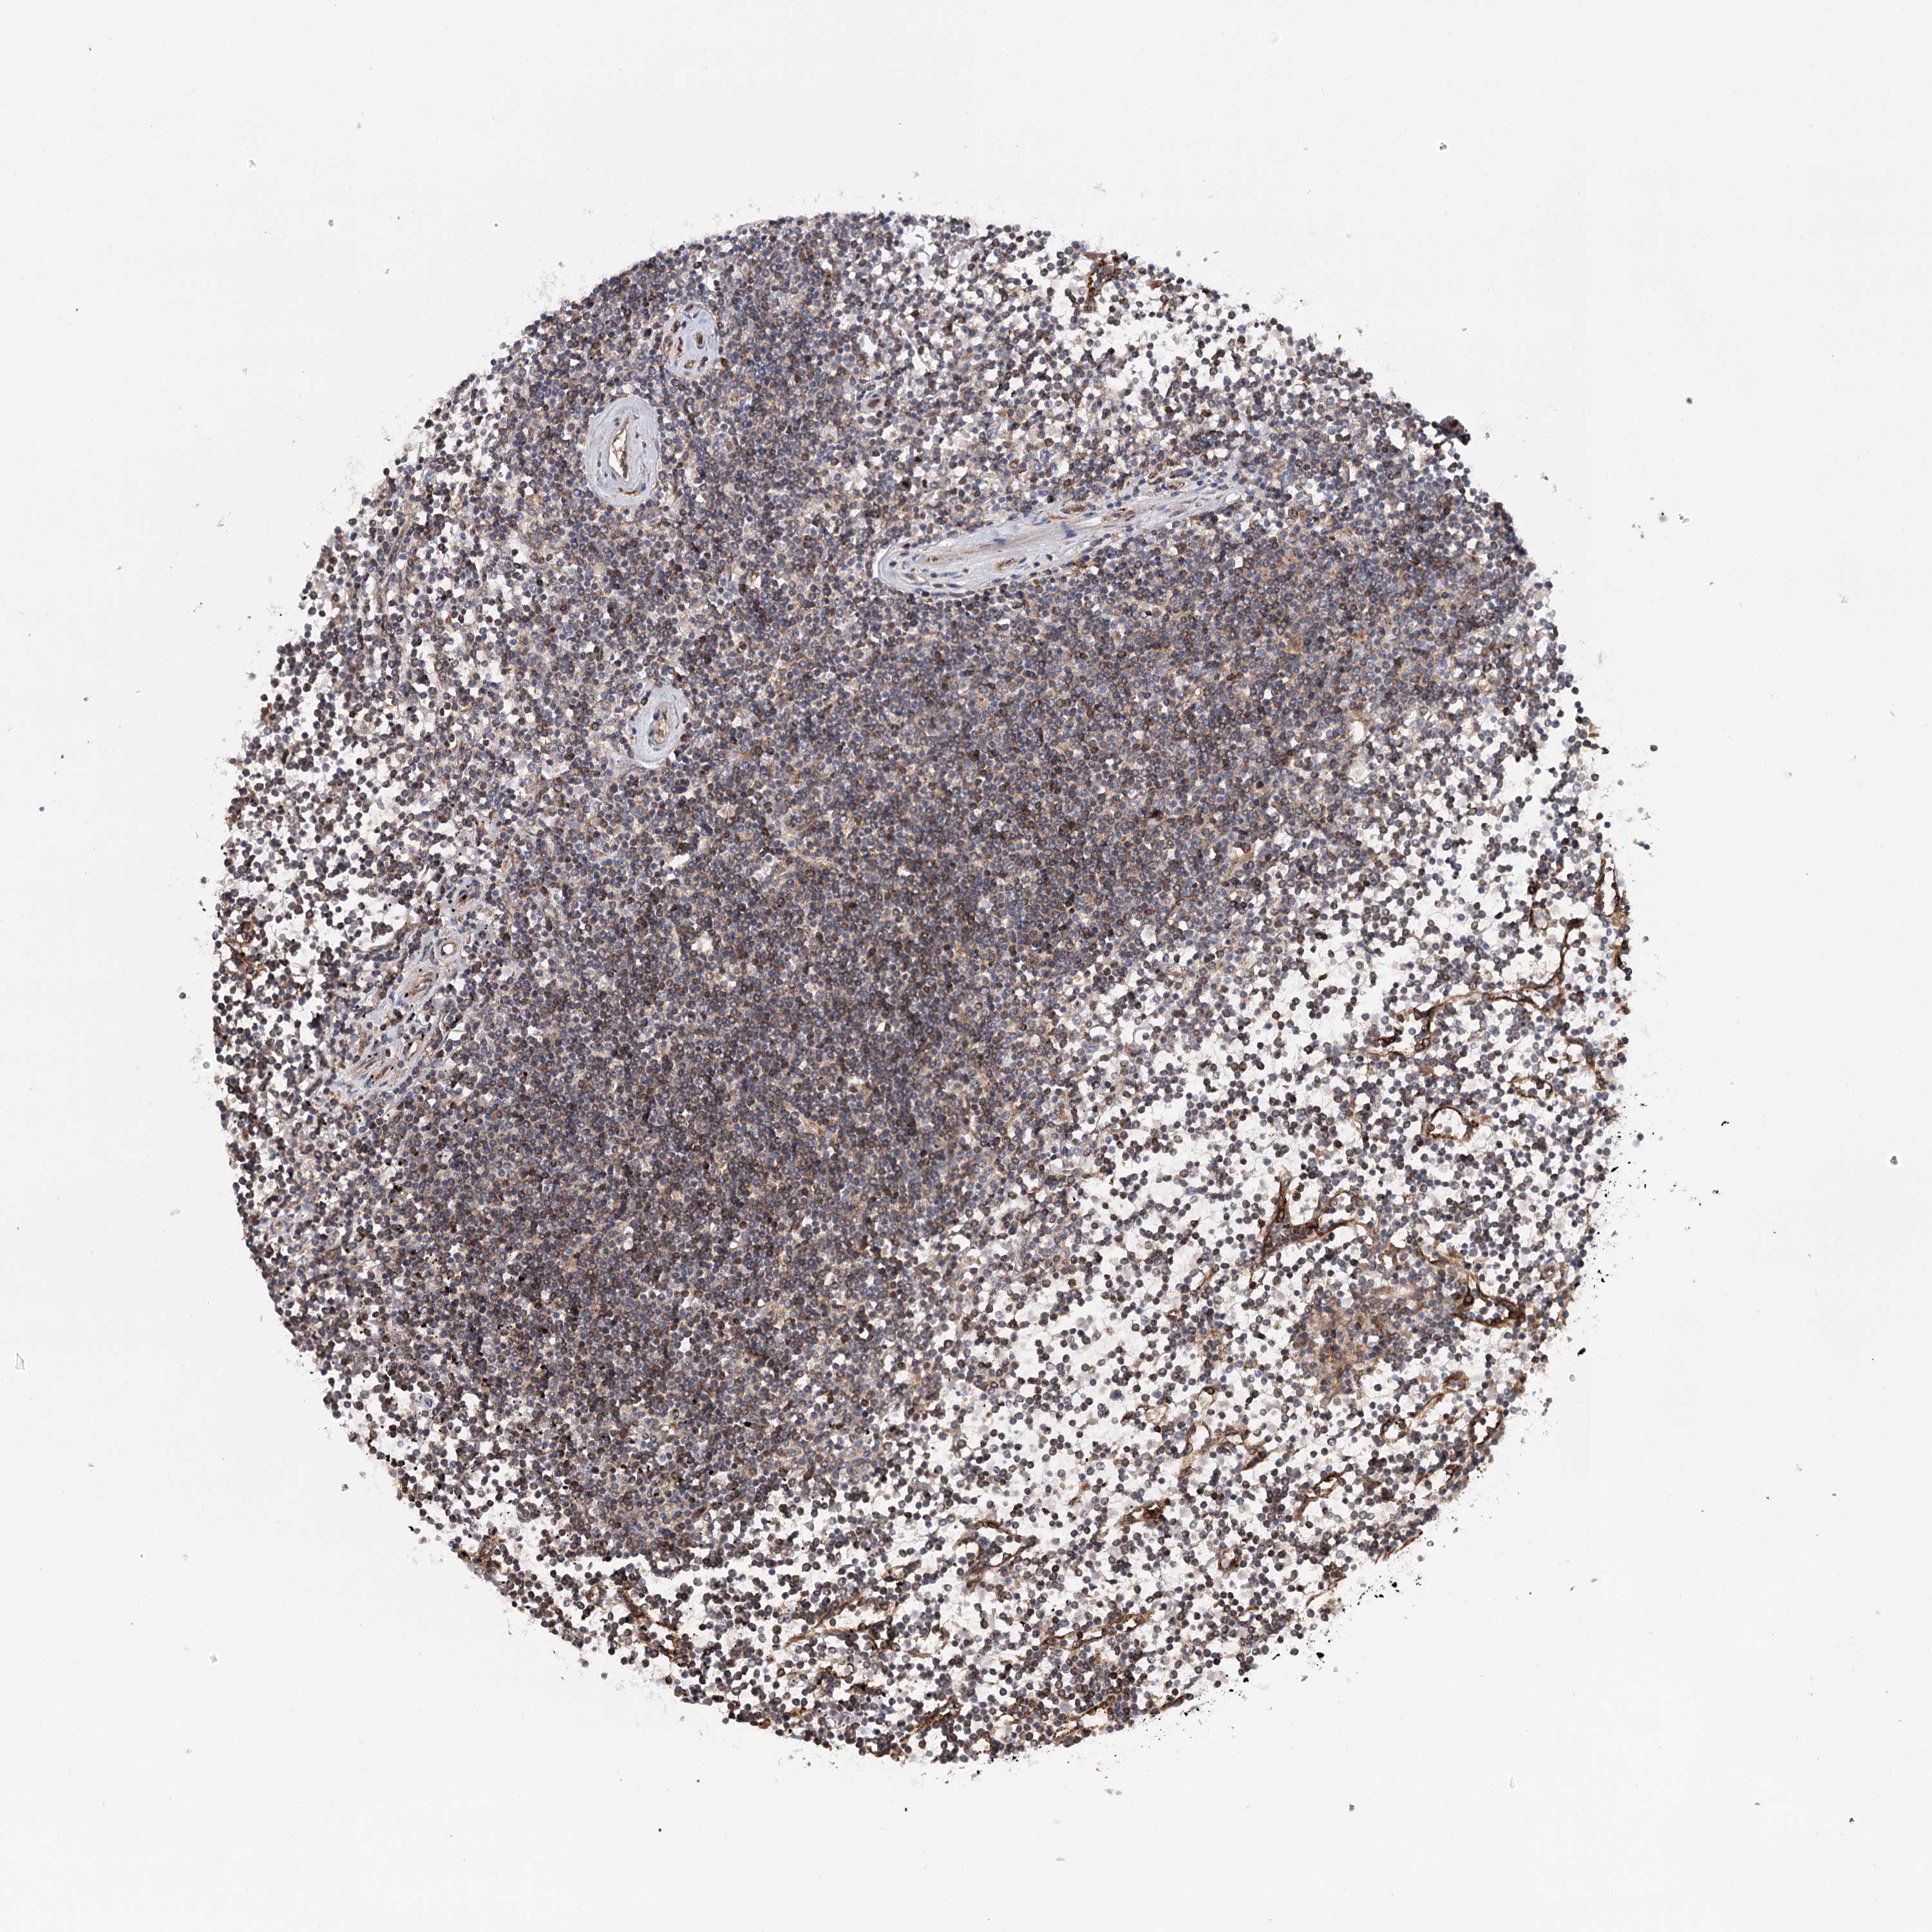

Lymphoma